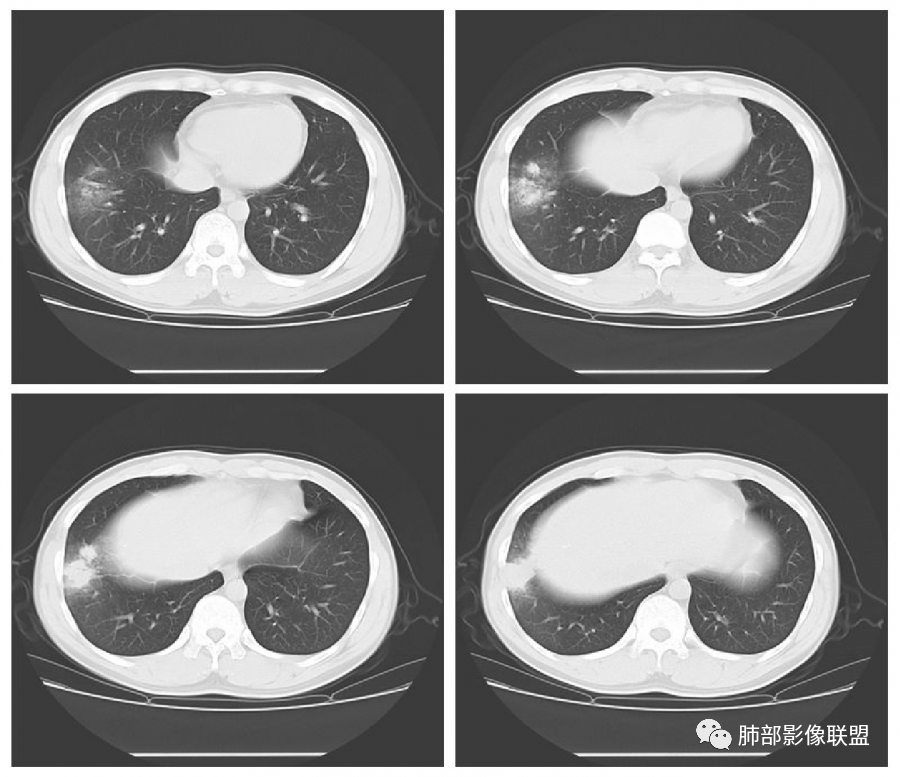

青年男性,急性病程,首次CT实变周围伴磨玻璃,边缘模糊,4天后病变明显进展大片状实变,边缘部可见磨玻璃影,内见支气管气象。考虑感染性病变,支原体?病毒?

初次右肺下叶斑片状磨玻璃及实变影,4天后复查明显进展,大片实变及磨玻璃,细网格,下叶近段支气管壁增厚,扩张,无胸腔积液,考虑社区获得性肺炎,病毒性肺炎?

右肺下叶片状高密度影,周围磨玻璃影,阿奇治疗无效,病变进展实变影增大,边缘膨隆伴多发间隔增厚,化验白细胞不高,淋巴细胞低,青年男性,咳嗽发热,考虑感染性病变,病毒性肺炎可能大。

青年男性,咳嗽咳痰发热4天,急性起病,抗感染治疗效果不佳,白细胞计数降低。第一次CT:右下叶斑片实变影伴磨玻璃影,边缘模糊。4天后复查CT:病变快速进展,右下叶大片实变影,内可见支气管充气征,边缘模糊,可见腺泡结节,叶间裂膨隆。考虑:大叶性感染,叶间裂膨隆,肺克?军团、病毒性肺炎无法除外。

青年男性,高热畏寒、咳嗽咳痰、咽痛、腹泻,白细胞及淋巴细胞降低,胸CT示实变+GGO,实变灶内可见支气管充气征,短期快速进展,气管壁不厚,无树芽树雾征,考虑病毒性感染。

青年男性,右肺下叶大片状实变,宽基底与胸膜相贴,糊墙,见支气管充气征,叶间裂膨隆,胸水不明显,短期迅速进展,支持感染性病变,阿奇霉素治疗无效,白细胞降低,首先考虑病毒性肺炎,军团菌印象是多叶受累,待排吧。

患者青年男性,急性起病且使用抗菌素治疗后仍快速进展,主要症状表现为咳嗽、咳痰、畏寒、发热4天。血常规:白细胞及淋巴细胞降低。胸部CT:右下肺背段+基底段可见实变+GGO+支气管充气征,病灶位于胸膜外带下比靠近肺门处重,支气管壁未见增厚。诊断首先感染性疾病,腺病毒性肺炎可能性最大。

1. 青年男性,社区发病,无免疫缺陷病史;            2. 急性起病,春季为病毒感染高发季节;       3. 患者临床以高热、咳嗽、咳痰为主的呼吸道症状,而且进展迅速,这些都是提示肺部感染可能大,没有明显咽痛等上呼吸道感染症状,未检测出流感病毒,流感病毒可能性较小;      4. 白细胞和淋巴细胞减低,支原体肺炎和病毒性肺炎都可能,但是经阿奇霉素、派拉西林治疗后无明显效果,支原体肺炎和细菌性肺炎可能性小,病毒性肺炎可能较大;      5. 患者早期CT表现为斑片影,磨玻璃密度为主,小叶内间隔增厚均提示病灶为间质性改变为主,病毒性肺炎可能大。病灶迅速进展为实性密度为主,呈大叶性肺炎改变,并见成簇多结节或多片影,较符合腺病毒的影像改变。